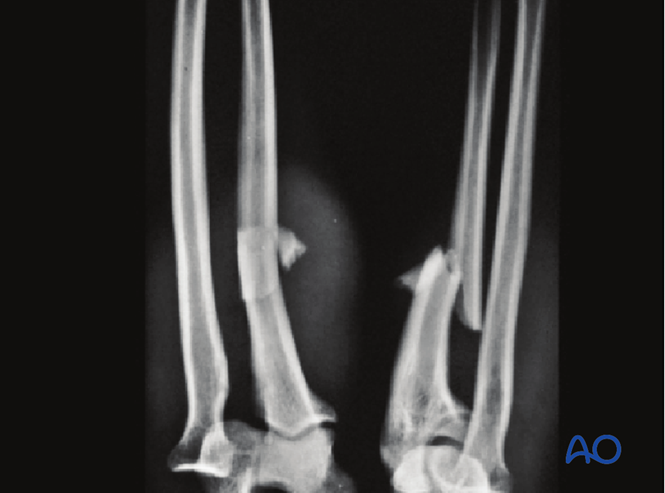

8. 病例

肘关节CT显示桡骨头向前脱位。

三维CT图像。

X线检查●应按照当地诊疗规范进行随访X线检查。建议在2周时进行X线检查,确保桡骨头位置保持良好,之后在6周、12周和1年时检查,评估尺骨愈合情况。●若X线显示尺骨愈合进展满意,约术后8周可开始负重。●该病例展示了孟氏骨折术前和术后的X线影像。

术前